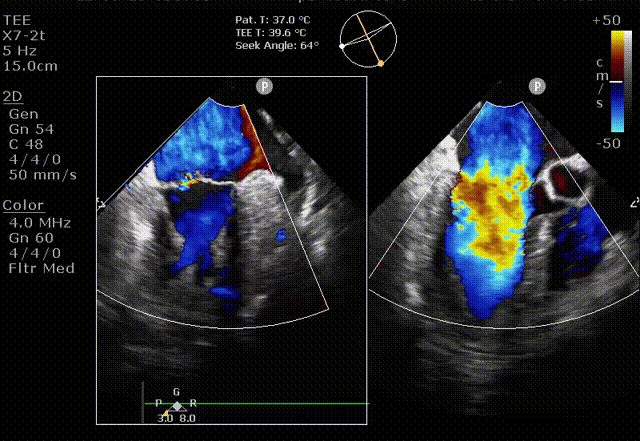

接受治疗的是一例二尖瓣重度反流的患者,主诉“突发间歇性胸闷,气急6天”。术前超声提示:1.二尖瓣脱垂伴重度关闭不全(瞬时量30ml);2.左心、右房增大(左房容积110ml,左室容积129ml,右房容积55ml);3.左室收缩功能正常。患者在充分标准化药物治疗后(GDMT)仍然症状明显,韩林教授及其团队唐杨烽教授,以及心超科的周广为医生决定使用我国创新器械JensClip为患者进行二尖瓣缘对缘修复手术。

术前超声

在阜外医院潘湘斌教授团队的支持下,手术经股静脉-房间隔入路,采用全身麻醉插管,在TEE和DSA引导下完成房间隔穿刺。置入JensClip瓣膜夹系统后,在左房调整瓣膜夹的位置和轴向,后进入左室,在TEE引导下捕捉二尖瓣前后瓣叶,并关闭瓣膜夹。经TEE反复确认手术效果后最终锁定并释放瓣膜夹。术后即刻超声显示瓣膜夹位置稳定,功能良好,二尖瓣反流由术前4+减少至微量,手术圆满成功。